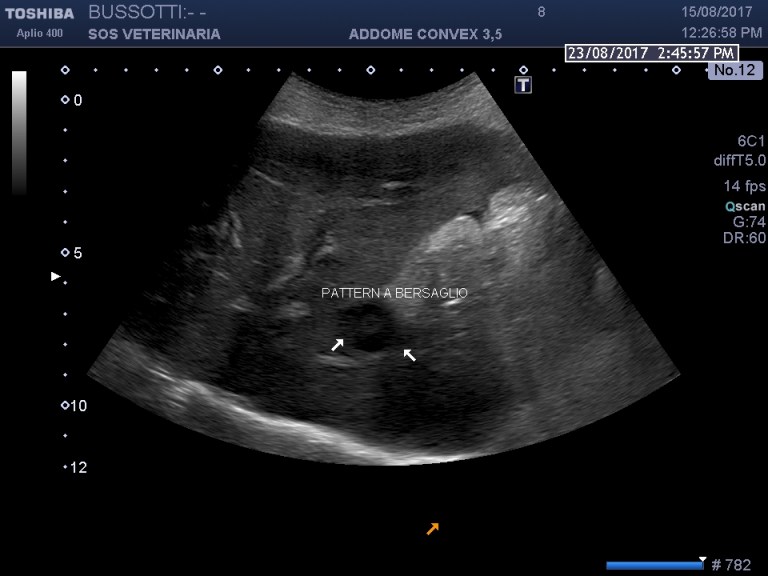

Evidenti alterazioni epatiche, colpisce la lesione focale a bersaglio,l irregolarita’ del profilo lobare ,il volume stimato aumentato ,la difficolta’ ad evidenziare le aree ventrali che sembrano essere ipoecogene e irregolari ,nel filmato verso gli ultimi frame si apprezza una massa retrogastrica verosimilmente linfocentrica meno probabile l interessamento del corpo pancreatico,

evidente la falda di fluido libero in addome campionata risultata essere ematica